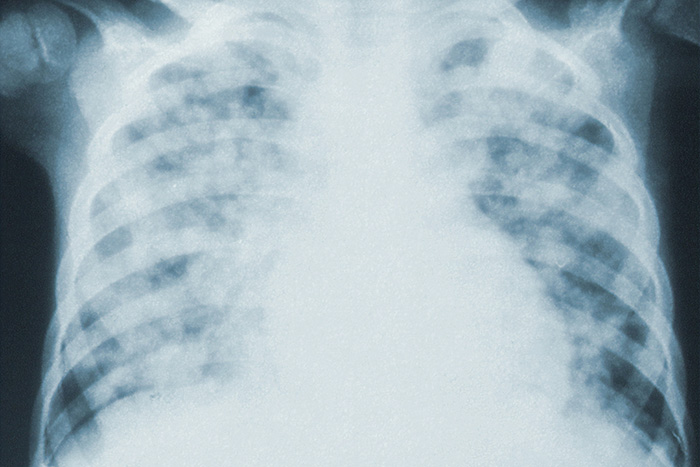

В комздраве пришли к такому выводу, так как высокая заболеваемость пневмониями не характерна для летних месяцев, но является основным осложнением COVID-19. По данным комитета, больные с пневмониями с легкими клиническим течением и поражением легких до 25 % проходили лечение дома, а с поражение легких более 25 % — в больницах. При этом не у всех пациентов с пневмониями удавалось лабораторно подтвердить коронавирус, поэтому многим диагноз ставили на основе характерной клинической картины и данных КТ.